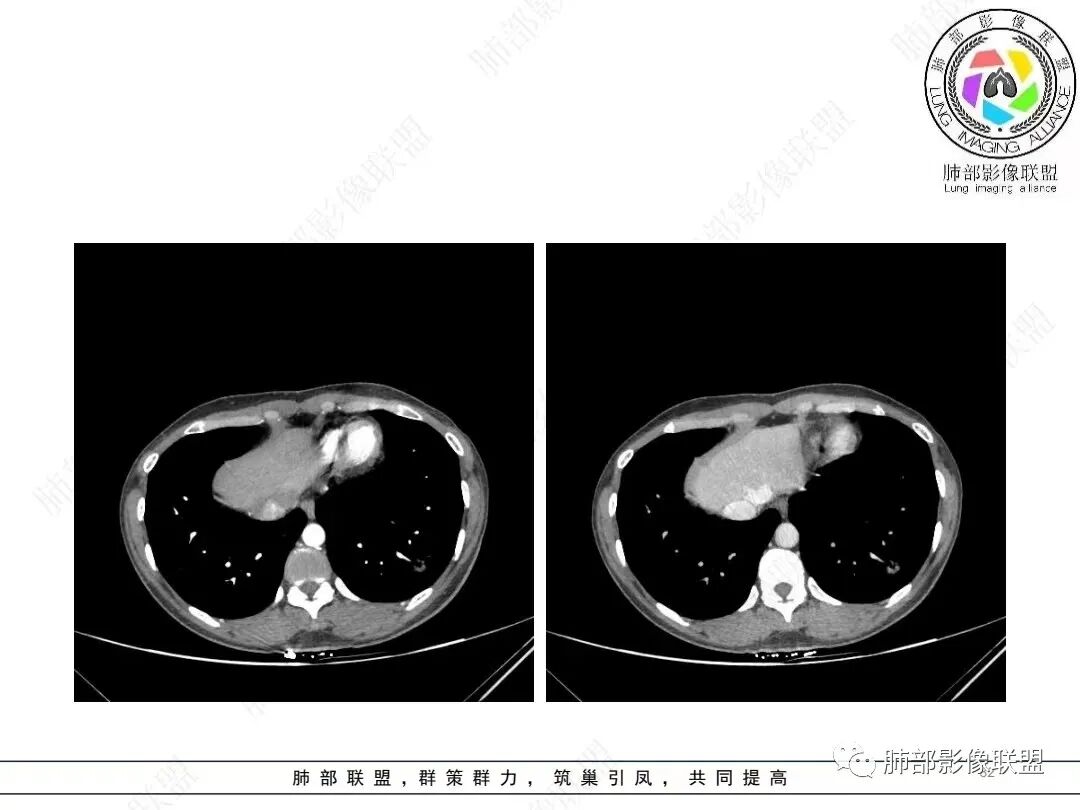

1、临床特点: 37岁女性,体检发现肺结节,2年前有甲状腺腺瘤手术史。实验室无阳性发现。

2、影像特点:左肺下叶类圆形结节影,周围可见多发细小毛刺,浅分叶,张力不高,未见胸膜牵拉。病灶内隐约见空泡影(未提供CT值),近端部分血管呈杵状增粗,可疑脐凹征。增强后实性部分有轻度强化。外围病灶,与支气管关系不明确。